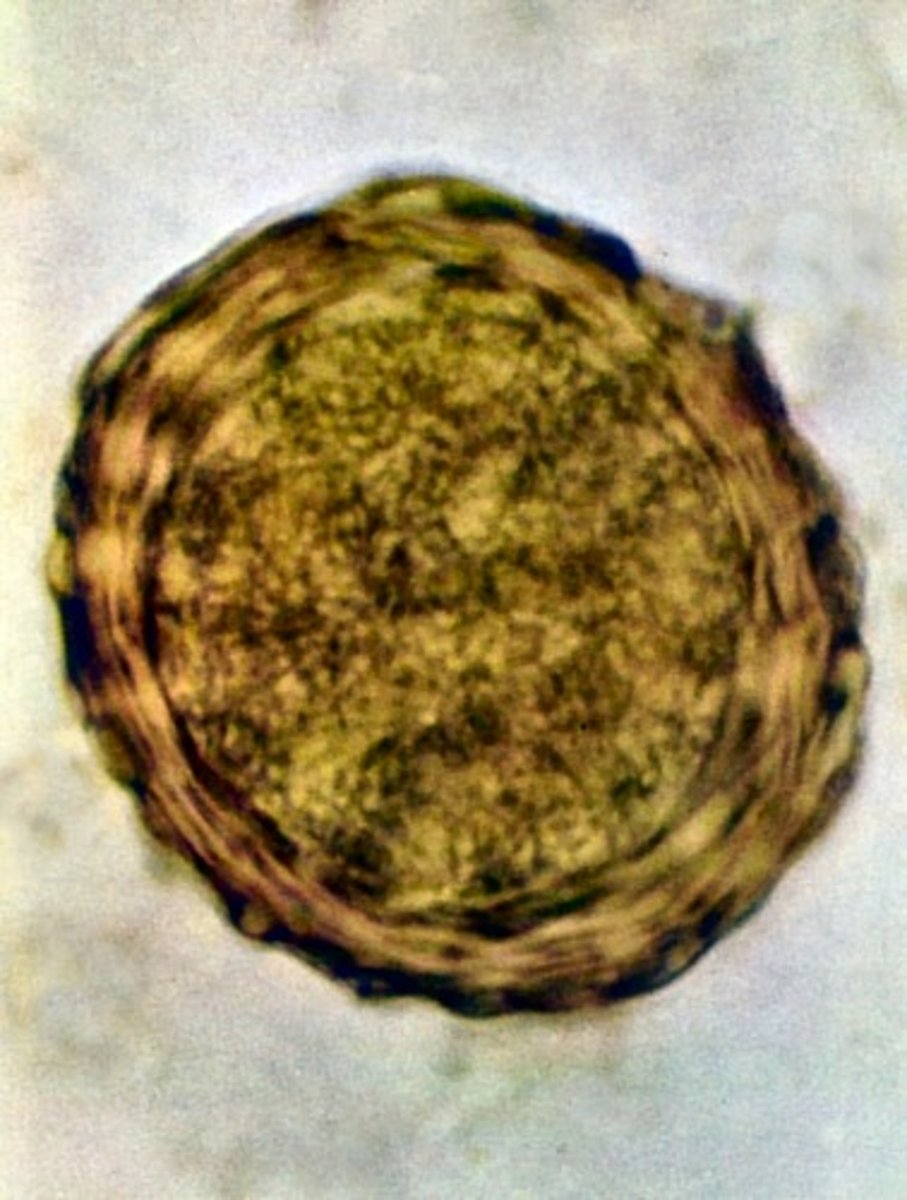

EGG: mammilations

-these eggs have mammillations meaning a curvy border!!!! whether fertilized or not. they can lose the mammilations sometimes and be called decorticated